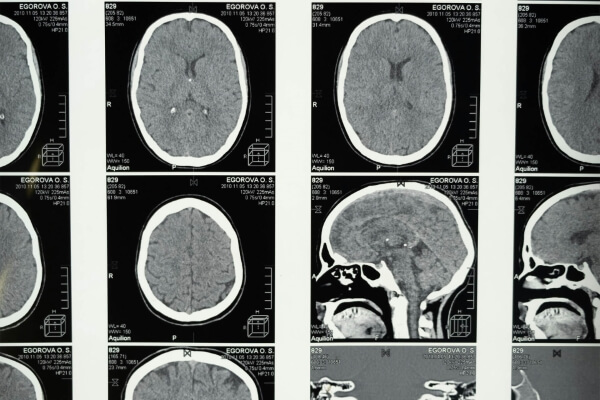

MRI Felvétel

Az MRI felvételek részletgazdagsága és pontossága alapvető fontosságú a különböző orvosi állapotok, például daganatok, gyulladások, degeneratív betegségek és sérülések azonosításában. Ezek a felvételek lehetővé teszik az orvos számára, hogy a lehető legpontosabb képet kapja a páciens állapotáról, így segítve a szükséges kezelések hatékony tervezését és végrehajtását.

Az MRI felvételek során a test bármely kiválasztott részéről részletes, háromdimenziós képek készülnek, amelyek tiszta és éles betekintést nyújtanak a vizsgált területekre. Ezek a felvételek kiemelik a szövetek, csontok, ízületek és belső szervek szerkezetét, valamint az esetleges elváltozásokat és betegségeket. Az MRI felvétel képessége, hogy különbséget tegyen a különböző típusú szövetek között, nélkülözhetetlen a precíz diagnózis felállításához és a kezelési terv megtervezéséhez.